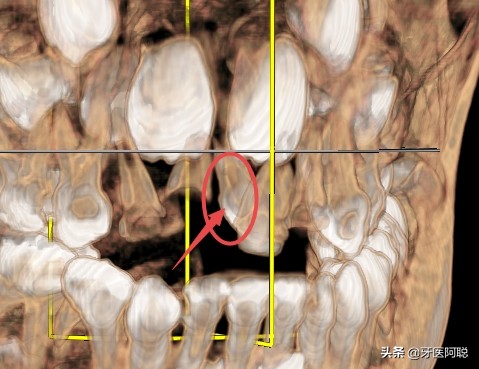

在儿童换牙期间,一旦发现有形态异常的牙时应请医生确诊。上颌门牙区的多生牙,若在门牙未萌出之前及早拔除,可以防止上门牙的错位生长。若该牙没有及时拔除,在门牙萌出后发现前牙拥挤畸形或门齿前突畸形,此时一定要拔除多生牙,让前牙自行调整。也可以戴矫正器或皮圈矫正。总之,多生牙是额外牙齿,在其刚一萌出,看其外观不正常,在拍牙片,认定为畸形多生牙后,应及早拔除。

在孩子还是一个胚胎的时候,会形成32颗恒牙蕾。但如果在恒牙形成的过程中孩子的牙板增殖剧烈,会形成超过正常数量的牙齿。在孩子出生以后成长的过程中,这个多余的牙齿也会长出来,就会形成多生牙。这样的牙齿,一般是在门牙处比较常见。